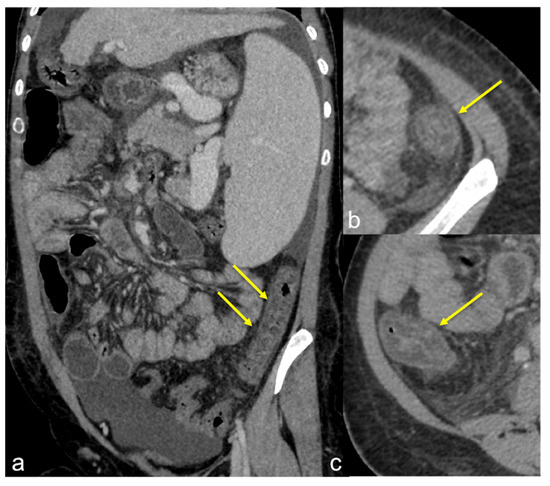

| Aorto-Enteric Fistula (Figure 31) | Bleeding in a patient with a history of surgery for aortic aneurysm. | A connection between the aorta and the intestinal lumen. Absence of adipose cleavage planes. |

| Haemobilia (Figure 32) | Melaena, haematemesis, biliary colic, jaundice, or massive bleeding in a patient with a history of blunt or iatrogenic abdominal trauma. | Presence of blood in the gallbladder and biliary tree. |